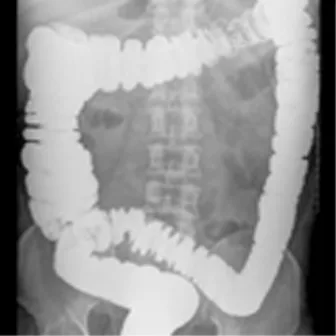

Stipsi: diagnosi differenziale – Criteri di Roma IV

La stipsi è un sintomo associato a vari disturbi funzionali gastrointestinali. Dal documento della Rome Foundation, una raccolta dei criteri diagnostici di alcuni quadri clinici, fra cui IBS e stipsi da oppioidi.